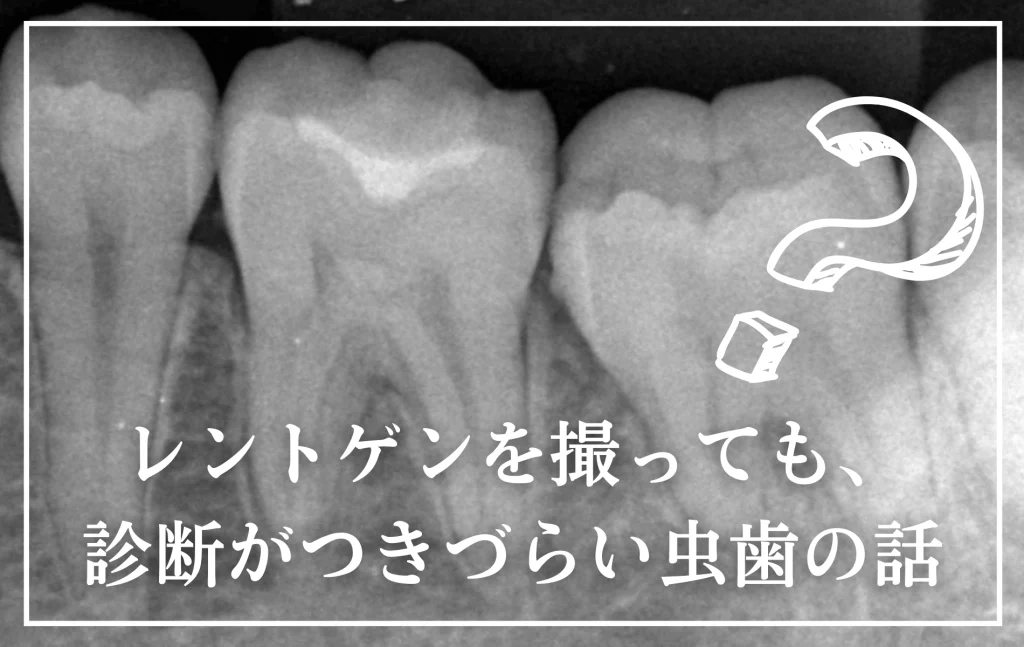

通常は、さし歯の中が虫歯になってしまうと、レントゲンにも写らず見つけづらいのですが・・・。

歯を裏側から見たところです。

幸い、見える部分に虫歯が

さし歯と歯肉の間に虫歯ができているのがわかります。

歯の奥まで虫歯が進んでいるのか、浅い虫歯ですんでいるのかは治療をしながら調べていく必要があります。